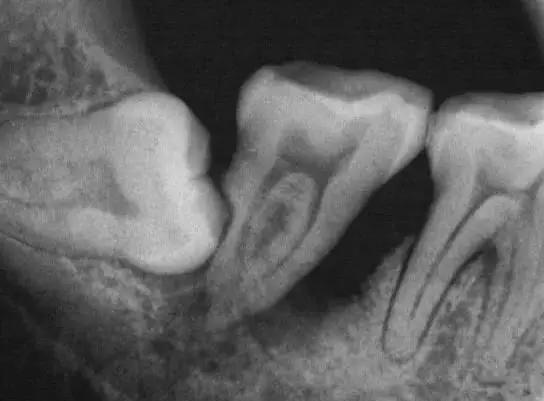

智齿萌发空间不足,常常会倒在第二磨牙上,因而造成第二磨牙清洁不易。智齿躺的时间一长,就会把旁边的邻牙都顶坏了,然后两颗都同归于尽。

这就是个玉石俱焚的案例。本来第一磨牙就缺失,智齿把第二磨牙也给顶牺牲了,种牙是在所难免了。